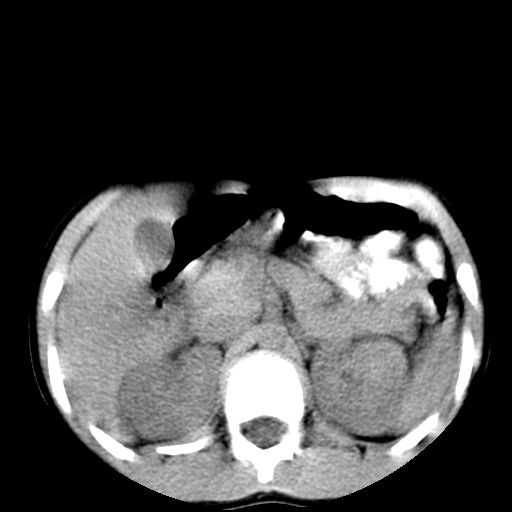

腹部好象未见异常。

腹部ct平扫未见明确异常

腹部ct平扫不能提示哪里有病变。